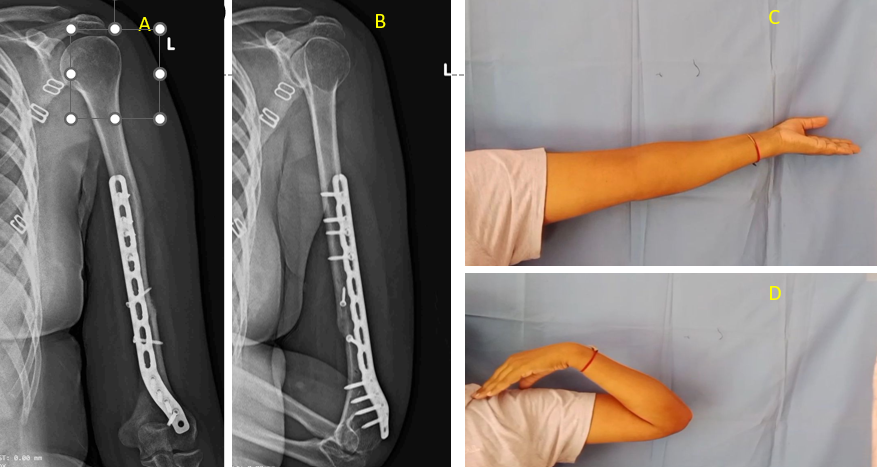

With fetal concerns resolved, the focus shifted to maternal recovery. Post-operative pain was effectively managed using multimodal analgesia, including scheduled paracetamol and a regional nerve block. Breastfeeding was successfully initiated, and sedation and opioid use were minimized to reduce the risk of neonatal respiratory depression [5]. Physiotherapy, including shoulder range-of-motion exercises, was started on post-operative day 2. Prophylactic anticoagulation was resumed 6 h after surgery, as post-operative bleeding remained minimal. By postpartum day 8, the mother and newborn were both stable. The surgical wound was clean, and the dressing was dry. At 6-week follow-up, early radiographic union was evident, and the patient had regained functional range of motion with only mild residual pain managed with non-opioid medications (Fig. 3).

Figure 3: Post-operative radiographic and functional outcomes following open reduction and internal fixation of a humeral shaft fracture. (a) Anteroposterior radiograph and (b) lateral radiograph demonstrating satisfactory fracture union with plate osteosynthesis. (c) Clinical photograph showing complete elbow extension, and (d) complete elbow flexion at follow-up, indicating restoration of functional range of motion.